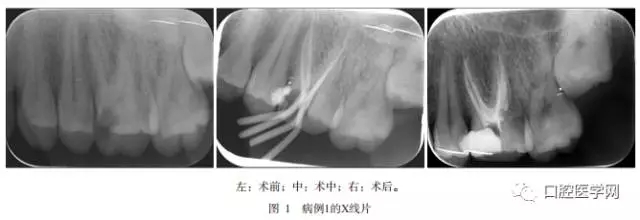

病例1,患者男,29歲,2013年3月因左上后牙冷熱刺激痛及夜間痛到青島市口腔醫(yī)院牙體牙髓科就診。患者1周前曾出現(xiàn)自發(fā)痛和放射至顏面部疼痛。檢查:左側(cè)上頜第一磨牙近中深齲已露髓,探診疼痛,叩診無疼痛,冷診疼痛,持續(xù)數(shù)十秒。X線片示:左側(cè)上頜第一磨牙面及近中面大面積低密度影像與髓角相連,根尖區(qū)未見明顯低密度影像,腭側(cè)根根管影像模糊不清,似與二頰根對(duì)稱分布(圖1左)。

待無癥狀和根管無滲出后,Mtwo機(jī)用鎳鈦器械(VDW公司,德國(guó))預(yù)備根管,25號(hào)0.6錐度主尖示尖(圖1中,圖2中),熱凝牙膠(KaVo公司,美國(guó))行根管充填術(shù)。術(shù)后X線片示患牙根充恰填(圖1右,圖2右)。術(shù)后3個(gè)月復(fù)查,患者無任何不適,X線片顯示根尖區(qū)未有病變發(fā)生,治療效果佳。